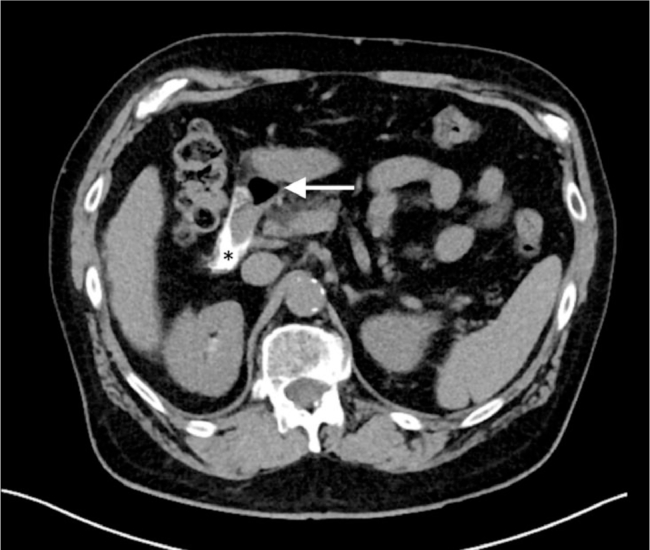

Fig. 2.

Unenhanced CT of the abdomen and pelvis 2 hours after the biopsy shows contrast (black asterisk) and foci of gas (white arrow) in the gallbladder fossa and porta hepatis indicating capsular penetration.